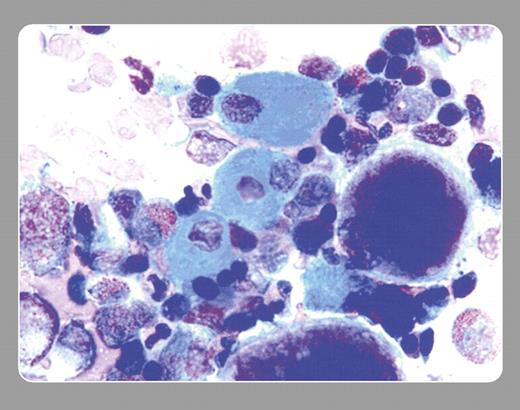

A bone marrow examination showed mild hypercellularity with myeloid hyperplasia and megaloblastic changes of the red cells. “Sea-blue histiocytes” were very prominently seen as well.

Sea-blue histiocytes, hepatosplenomegaly, and thrombocytopenia were reported in 1970 (Silverstein et al, N Engl J Med. 282:1-4). Similar histiocytes were reported in the liver, spleen, lymph nodes, and tonsils. Sea-blue histiocytes are also noted as a secondary phenomena of myeloproliferative disease, hyperlipidemia, lysosomal storage disease (Gaucher and Niemann-Pick), lymphoma, myelodysplastic disorders, with total parenteral nutrition, idiopathic thrombocytopenic purpura, and viral disorders.

The patient's medications were continued except for valproate. Shortly thereafter, her complete blood count normalized. One month later the marrow was repeated, and sea-blue histiocytes had disappeared. An association between sea-blue histiocytes and a drug, such as valproic acid, has not yet been reported.